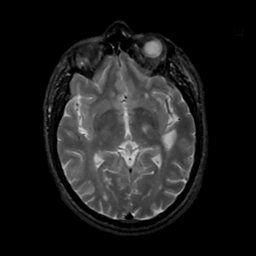

MR Study #15, June 9, 1991 -- Slice #24